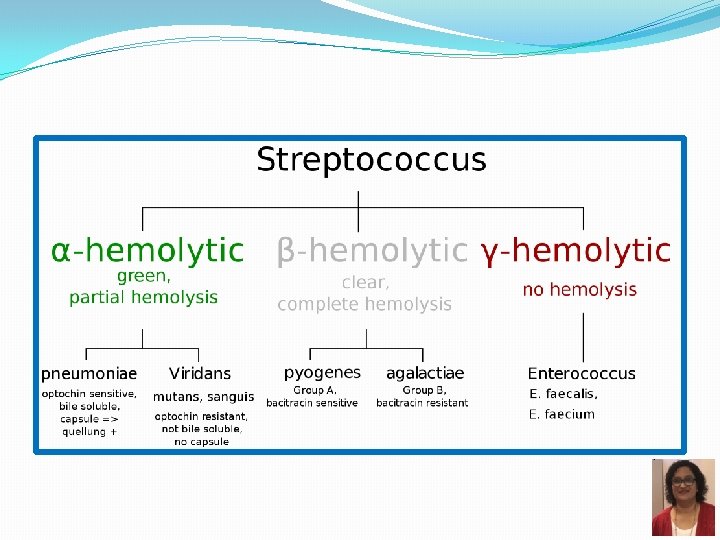

Community acquired Typical vs Atypical pneumonia Typical Atypical Ø Pneumonia with typical features Ø C/F: high fever, chest pain, cough which is usually productive, shortness of breath, lobar consolidation on Chest Xray Ø Bacteria: � Streptococcus pneumoniae � Hemophilus influenzae � Klebsiella pneumoniae � Moraxella catarrhalis � Staphylococcus aureus Ø Pneumonia with atypical features Ø C/F: Less severe illness, dry cough, headache, and other systemic complaints, patchy bronchopneumonia Ø Bacteria: � Chlamydophila species � Mycoplasma pneumoniae � Legionella pneumoniae � Coxiella burnetii Ø Viruses

Growth characteristics and identification α hemolytic colonies on blood agar/ Chocolate agar Catalase negative Optochin sensitive Bile soluble